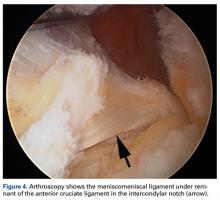

Arthroscopy of the left knee was performed for reconstruction of the ACL and repair of the menisci ( Figures 3, 4 ). The suprapatellar pouch and medial and lateral gutters were normal. There was grade 2 fraying of the distal portion of the trochlea medially and laterally in the medial facet of the patella. An aberrant anterior horn medial meniscus attachment was found; it had been interpreted as a tear on MRI. This aberrancy ran through the femoral intercondylar notch and attached to the posterior horn of the lateral meniscus ( Figures 5A-5H ) ( watch the video ).Discussion

The medial and lateral menisci typically are separate fibrocartilaginous structures acting as a cushion for the knee, but normal variant connections between the structures have been described. These connections include the anterior transverse meniscal ligament, the posterior transverse meniscal ligament, and the medial and lateral oblique meniscomeniscal ligaments. 3 In the present case, a medial oblique meniscomeniscal ligament was identified. Its path between menisci was traceable on coronal and axial views. Video taken during arthroscopy also clearly showed its path and its relationship to other structures in the knee. To Dr. Flanigan’s knowledge, this ligament was not previously described with video. It is important to distinguish this ligament from a horizontal tear of the meniscus, given the potential for misinterpretation on MRI. A horizontal tear is a degenerative change that often occurs in older patients. Our patient was 18 years old at time of injury. In addition, the surface of his lower meniscus was smooth, whereas in a tear the edge is irregular and discontinuous. Dr. Flanigan prefers to leave this ligament intact unless resection would provide better visualization during arthroscopy. His reasoning is that the functional characteristics of the ligament are not well understood.